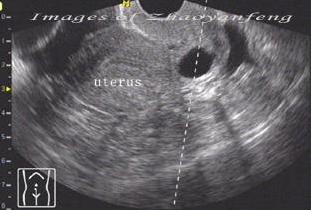

宫颈囊肿的B超诊断表现:检查时可以看到宫颈表面突出多个大小不一的青白色囊泡(并非紫色),内含黏液,小的有米粒大,大的有玉米粒大,有的可以长得很大,突出于宫颈表面,甚至到达阴道口,根部与宫颈之间有蒂相连,常合并有宫颈肥大。